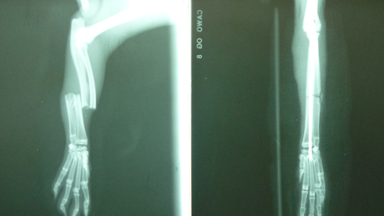

Röntgen von allen Kleintieren von 5 g bis 80 kg